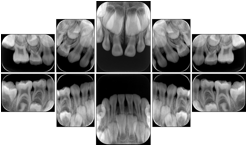

In most standard cases, images are oriented in structured layouts. These structured displays are useful to be shared between providers for reference purposes.

Table OO.1.1-1 shows structured display standard templates, where Viewset ID is based on the Japanese Society for Oral and Maxillofacial Radiology (JSOMR) classification provided by JIRA (Japan Medical Imaging and Radiological Systems Industries Association, www.jira-net.or.jp). Expected or typical teeth to be imaged location, region and designation codes are based on ISO 3950-2010, Dentistry - Designation system for teeth and areas of the oral cavity. For all the hanging protocols listed in OO.1.1-1, the value to use for Hanging Protocol Creator (0072,0008) is "JSOMR" and the value to use for Hanging Protocol Name (0072,0002) does not include "JSOMR" (e.g., "DL-S001A", not "JSOMR DL-S001A").